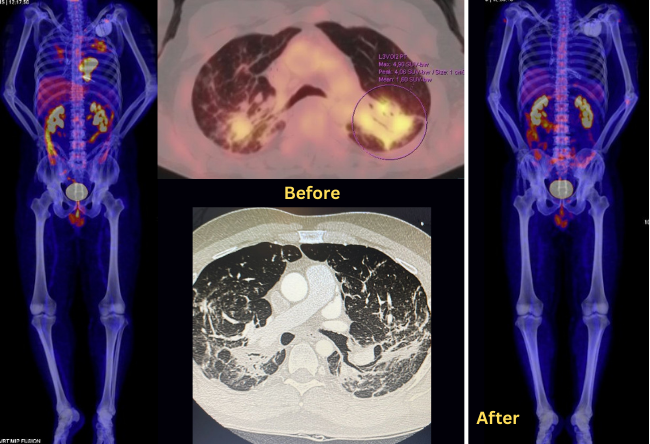

.png) Fluorine 18 fluorodeoxyglucose (FDG) PET/CT at diagnosis with cardiac and pulmonary impairment. PET-CT after treatment without cardiac or pulmonary uptake.

Fluorine 18 fluorodeoxyglucose (FDG) PET/CT at diagnosis with cardiac and pulmonary impairment. PET-CT after treatment without cardiac or pulmonary uptake.